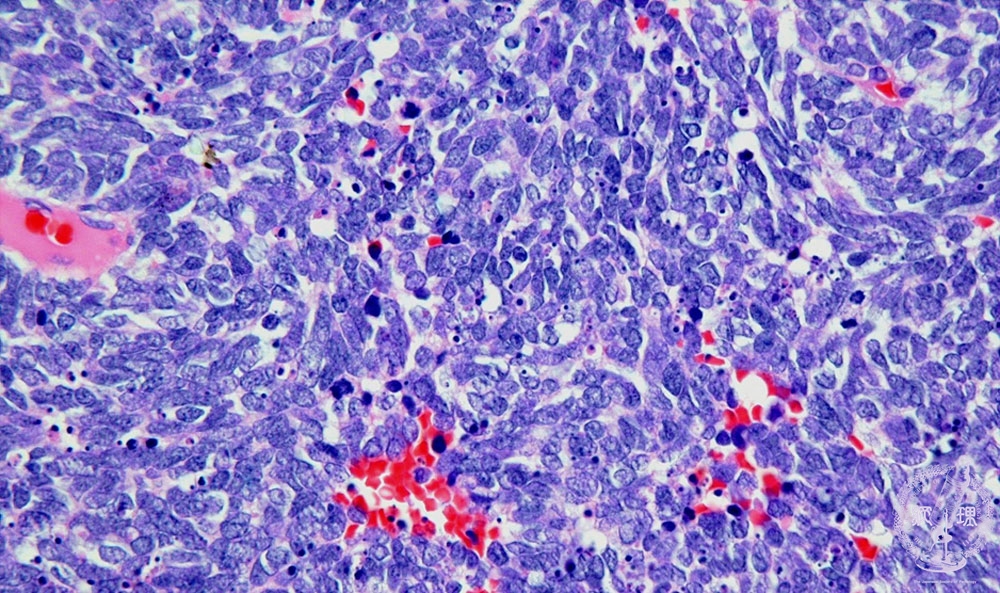

- ★(18)Small cell carcinoma

Microscopic view (HE stain, high power view): Small cell carcinoma of lung. Carcinoma cells have scant cytoplasm and a high N/C ratio. Many mitotic (arrow) and apoptotic (arrow head) figures are seen indicating high proliferative activity.